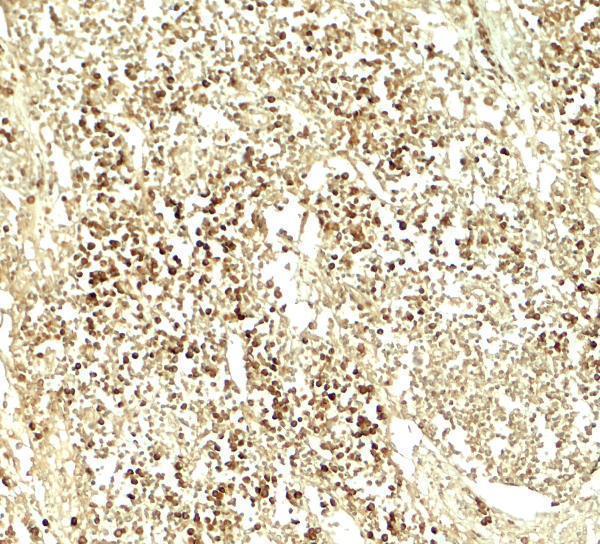

Facts about Transcription factor E2F3.

E2F3 binds specifically to RB1 in a cell-cycle dependent way. Inhibits adipogenesis, likely through the repression of CEBPA binding to its target gene promoters (By similarity).